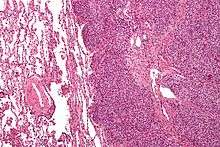

Ewing's sarcoma is a small-blue-round-cell tumor that typically has a clear cytoplasm on H&E staining, due to glycogen. The presence of the glycogen can be demonstrated with positive PAS staining and negative PAS diastase staining. The characteristic immunostain is CD99, which diffusely marks the cell membrane. Morphologic and immunohistochemical findings are corroborated with an associated chromosomal translocation, of which several occur. The most common translocation, present in about 90% of Ewing sarcoma cases, is t(11;22)(q24;q12),[12][13] which generates an aberrant transcription factor through fusion of the EWSR1 gene with the FLI1 gene.[14]

The pathologic differential diagnosis is the grouping of small-blue-round-cell tumors, which includes lymphoma, alveolar rhabdomyosarcoma, and desmoplastic small round cell tumor, among others.